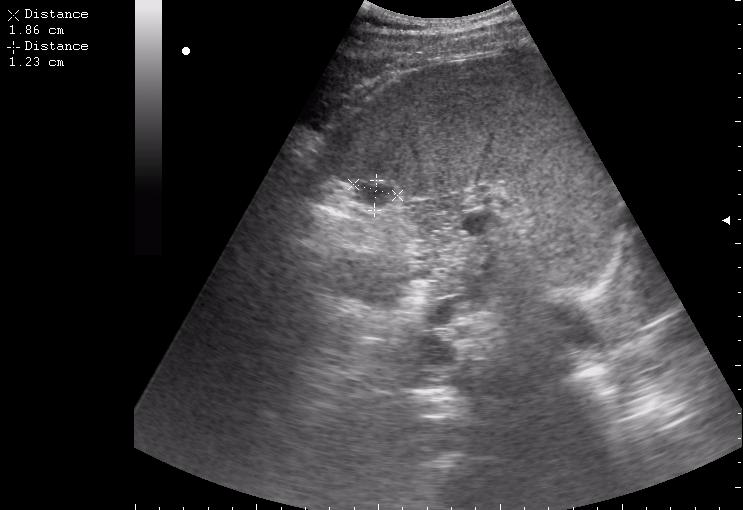

>желтой стрелкой - это левый надпочечник?

Похоже.

Он обычно располагается больше кнутри от верхнего полюса почки и может досигать ее ворот.

Надежнее визуализировать ЛН из позиции, которую я показывал в известной Вам теме.